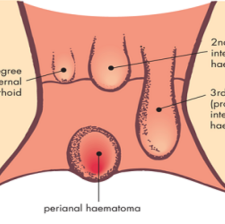

Perianal Hematoma

A perianal hematoma is a collection of blood that has leaked from a burst blood vessel in the area around the anus. This blood pools up outside the blood vessel below the surface of the skin, although it is possible to see the characteristic dark-blue discoloration with the naked eye.

Piles

Hemorrhoids (HEM-uh-roids), also called piles, are swollen veins in the anus and lower rectum. Hemorrhoids are similar to varicose veins. Hemorrhoids can develop inside the rectum, called internal hemorrhoids. They also can develop under the skin ar